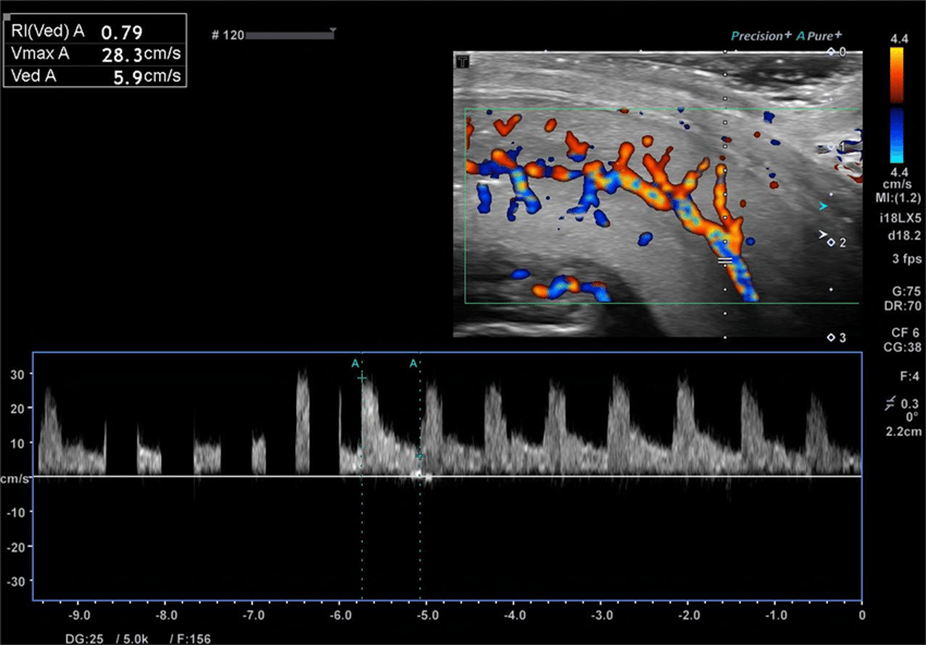

Dynamic Penile Color Doppler Ultrasound

One of the most important tests in the diagnosis of sexual impotence is the dynamic penile color Doppler ultrasound. This examination allows the evaluation of:

- penile arterial blood flow

- possible circulatory problems

- the presence of venous leakage

It is particularly useful in young patients or when a vascular cause is suspected.